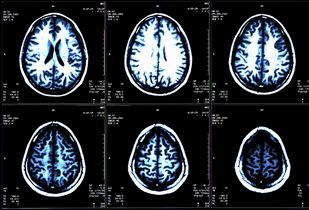

Alemtuzumab improved clinical and magnetic resonance imagining outcomes in patients with relapsing-remitting multiple sclerosis across varying age groups and maintained efficacy through year 8 of follow up.

Cortical lesions play a major role in the progression of multiple sclerosis (MS). A recent study looked to longitudinally characterize the development and evolution of cortical lesions in MS across the cortical width, as well as their relationship with white matter lesion accrual.